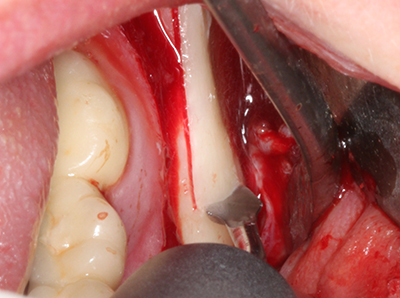

Indication: Preparation near nerves

As noted above, indications for piezo surgery can also be found in the field of conservative dental surgery. Special working tips simplify the exposure of root tips and make it easier to protect nerves and sinus mucous membranes, particularly in the lower premolar and upper posterior tooth regions. Angled diamond tips are used to precisely prepare the resection cavity for the retrograde root filler material for unsealed apical obturation. The ultrasonic technology means the tips can be very slender, which improves the view and the size of the access cavity. As a result, the application of ultrasonic surgery for this indication is one of the standard procedures for apical resection (Del Fabbro, Tsesis et al. 2010, Scarano, Artese et al. 2012).

Indication: Apical resection

When surgical procedures are performed on bone in the immediate vicinity of sensitive structures such as blood vessels or nerves, rotary instruments pose a significant risk of iatrogenic injury. Piezoelectric devices can be helpful for preparation of bone covers and removal of hard tissue close to nerves, particularly for exposure of nerves after iatrogenic injury but also during nerve lateralization for resective and reconstructive procedures or implant placement (Fig. 17-20). Light contact between the piezotip and the nerve does not generally result in damage but proceeding incautiously with saw-like motions or attachments where a residual bone substrate remains may cause temporary or even permanent nerve damage. However, the risk of damage is considered to be substantially lower than when using saws or milling instruments (Pereira, Gealh et al. 2014).